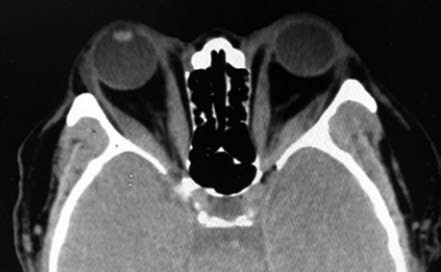

Figure 1 Thyroid eye disease

CT imaging shows bilateral proptosis with fusiform thickening of the medial rectus muscles.